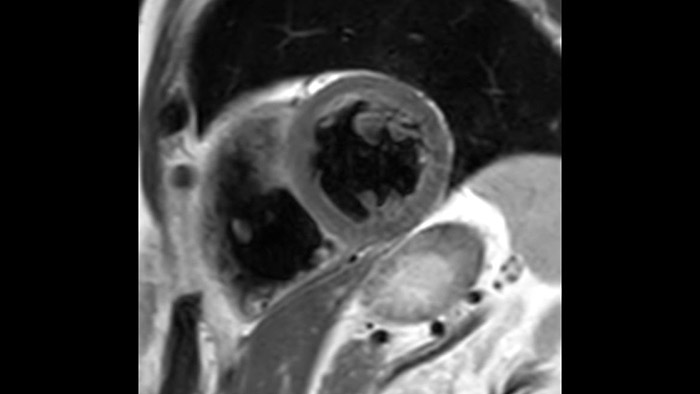

La diagnostica odierna spesso non è in grado di rilevare le disfunzioni cardiache fino a quando non si manifestano sintomi. MyoStrain valuta la deformazione del miocardio in 48 segmenti cardiaci e fornisce ai medici uno strumento diagnostico utile per identificare con anticipo la disfunzione funzionale prima che il cuore nel suo complesso sia compromesso.

La diagnostica tradizionale non offre la visibilità necessaria per vedere gli effetti di un trattamento cardiaco o individuare disfunzioni prima che si verifichino i sintomi. Combinando la sequenza di acquisizione MRI Fast-SENC di Philips con lo strumento di analisi MyoStrain di Myocardial Solutions, i lievi cambiamenti precoci nella funzione cardiaca possono essere misurati direttamente.